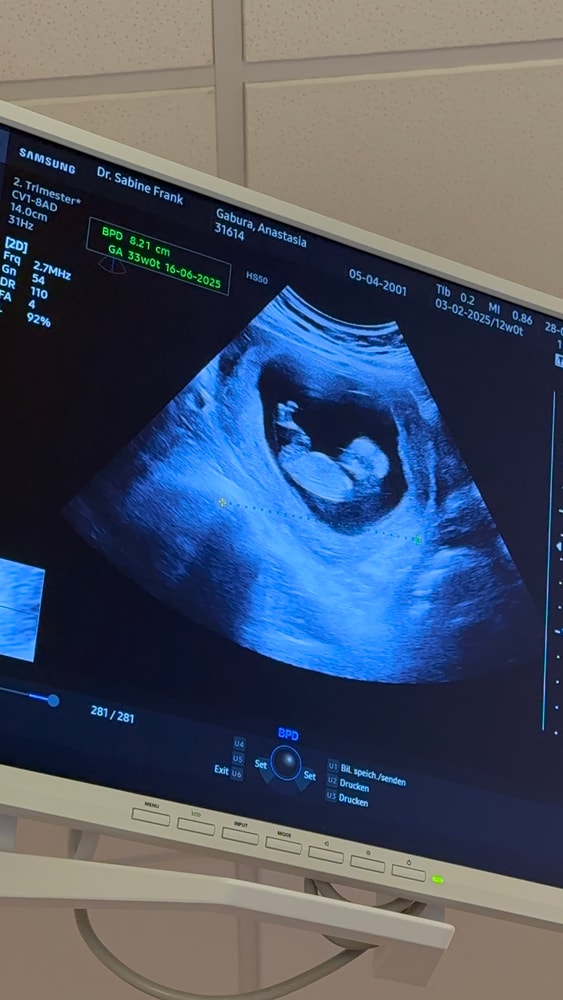

12 недель

Здравствуйте. Срок по месячным -12 недель

срок по размеру плода 11 и 4 .

плохо ли это ?

и размер плода составляет :4,8 см

норма или что-то не так ?